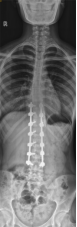

8. 机器人导航辅助下脊柱侧弯矫正技术

脊柱侧弯是一种复杂的脊柱三维畸形,其中以青少年特发性脊柱侧凸最常见。我院在浦口地区率先开展机器人导航辅助下脊柱侧弯矫正术,实现了脊柱侧弯手术准确、微创、智能化的突破,获得了良好的效果。还有老年人退变性侧弯,机器人亦可精准置入困难椎弓根螺钉,误差只有0.3mm。